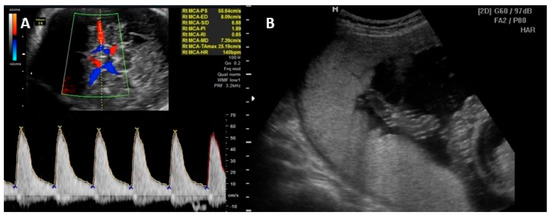

Parvovirus B19 infection is unlikely the cause of fetal anemia in the absence of ultrasound changes suggestive of fetal sequelae 8 to 12 weeks after possible exposure. Cordocentesis with fetal blood sampling to determine fetal hematocrit and intrauterine transfusion may be required in cases of fetal hydrops or severe fetal anemia [46,47,48,49]. Other signs of fetal parvovirus B19 infection include fetal ascites and cardiomegaly. Generalized edema and pericardial effusion occur in more advanced stages of the disease. Hyperechogenic bowel, meconium peritonitis, increased nuchal translucency in the first trimester, and amniotic fluid abnormalities have also been reported as US anomalies [50,51,52]. Figure 2 illustrates the PVS-MCA measurement and the intrauterine transfusion.

Figure 2.

(A) Peak of systolic velocity of the middle cerebral artery Doppler measurement technique. (B) Intrauterine transfusion with the needle in the vein at level of umbilical cord insertion on placenta.